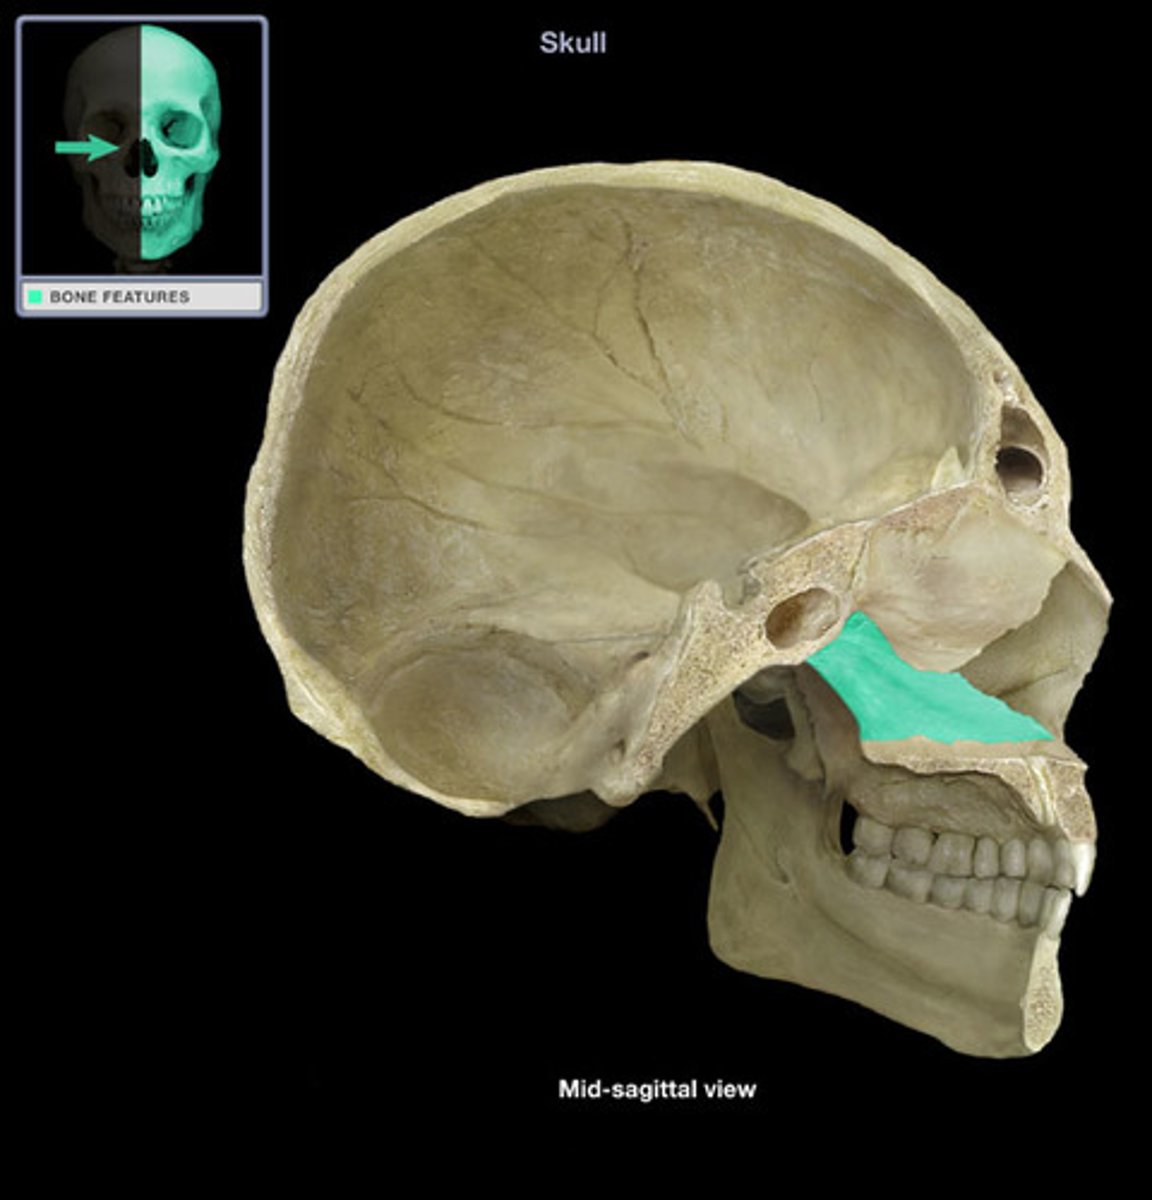

Cranium anatomy

anterior cranial fossa

middle cranial fossa

posterior cranial fossa

sphenoid bone

lesser wings

greater wings

pterygoid processes

sella turcica

tuberculum sellae

dorsum sellae

posterior clinoid processes

optic foramen

clivus

occipital bone

occipital condyles

foramen magnum

external occipital protuberance

jugular foramen

temporal bone

zygomatic process

mastoid process

styloid process of temporal

palatine bones

inferior nasal conchae

superior & middle nasal conchae

vomer